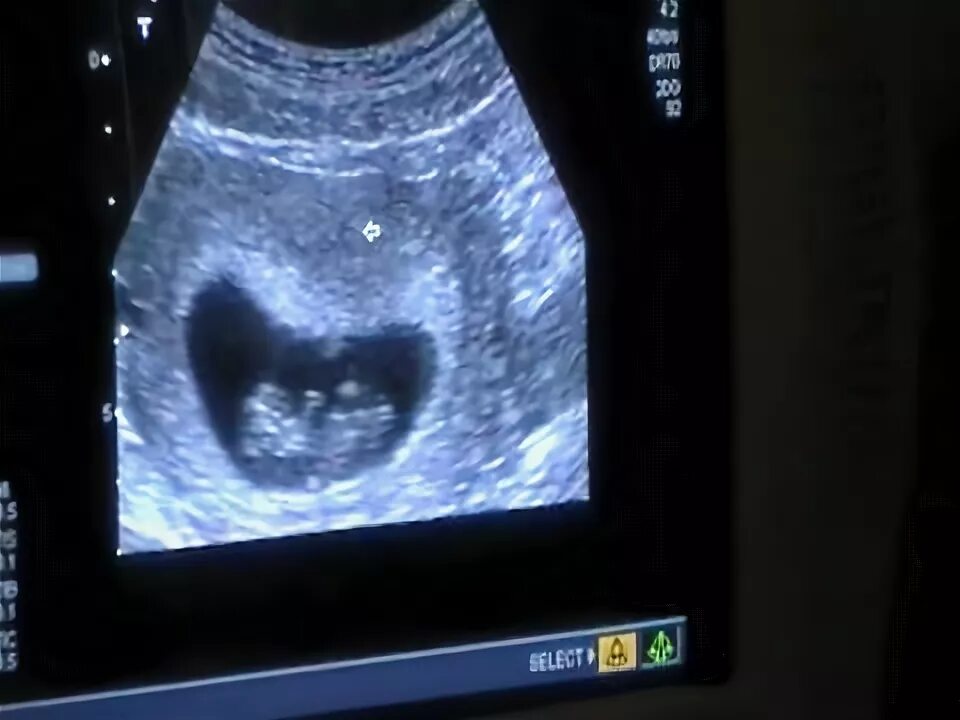

Was 10 in weeks